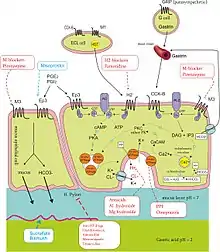

Helicobacter pylori is one of the major causative factors of peptic ulcer disease. It secretes urease to create an alkaline environment, which is suitable for its survival. It expresses blood group antigen-binding adhesin (BabA) and outer inflammatory protein adhesin (OipA), which enables it to attach to the gastric epithelium. The bacterium also expresses virulence factors such as CagA and PicB, which cause stomach mucosal inflammation. The VacA gene encodes for vacuolating cytotoxin, but its mechanism of causing peptic ulcers is unclear. Such stomach mucosal inflammation can be associated with hyperchlorhydria (increased stomach acid secretion) or hypochlorhydria (reduced stomach acid secretion). Inflammatory cytokines inhibit the parietal cell acid secretion. H. pylori also secretes certain products that inhibit hydrogen potassium ATPase; activate calcitonin gene-related peptide sensory neurons, which increases somatostatin secretion to inhibit acid production by parietal cells; and inhibit gastrin secretion. This reduction in acid production causes gastric ulcers.[14] On the other hand, increased acid production at the pyloric antrum is associated with duodenal ulcers in 10% to 15% of H. pylori infection cases. In this case, somatostatin production is reduced and gastrin production is increased, leading to increased histamine secretion from the enterochromaffin cells, thus increasing acid production. An acidic environment at the antrum causes metaplasia of the duodenal cells, causing duodenal ulcers.[14]

NSAIDs

Taking nonsteroidal anti-inflammatory drugs (NSAIDs) such as aspirin[22] can increase the risk of peptic ulcer disease by four times compared to non-users. The risk of getting a peptic ulcer is two times for aspirin users. Risk of bleeding increases if NSAIDs are combined with selective serotonin reuptake inhibitor (SSRI), corticosteroids, antimineralocorticoids, and anticoagulants. The gastric mucosa protects itself from gastric acid with a layer of mucus, the secretion of which is stimulated by certain prostaglandins. NSAIDs block the function of cyclooxygenase 1 (COX-1), which is essential for the production of these prostaglandins. Besides this, NSAIDs also inhibit stomach mucosa cells proliferation and mucosal blood flow, reducing bicarbonate and mucus secretion, which reduces the integrity of the mucosa. Another type of NSAIDs, called COX-2 selective anti-inflammatory drugs (such as celecoxib), preferentially inhibit COX-2, which is less essential in the gastric mucosa. This reduces the probability of getting peptic ulcers; however, it can still delay ulcer healing for those who already have a peptic ulcer.[14] Peptic ulcers caused by NSAIDs differ from those caused by H. pylori as the latter's appear as a consequence of inflammation of the mucosa (presence of neutrophil and submucosal edema), the former instead as a consequence of a direct damage of the NSAID molecule against COX enzymes, altering the hydrophobic state of the mucus, the permeability of the lining epithelium and mitochondrial machinery of the cell itself. In this way NSAID's ulcers tend to complicate faster and dig deeper in the tissue causing more complications, often asymptomatically until a great portion of the tissue is involved.